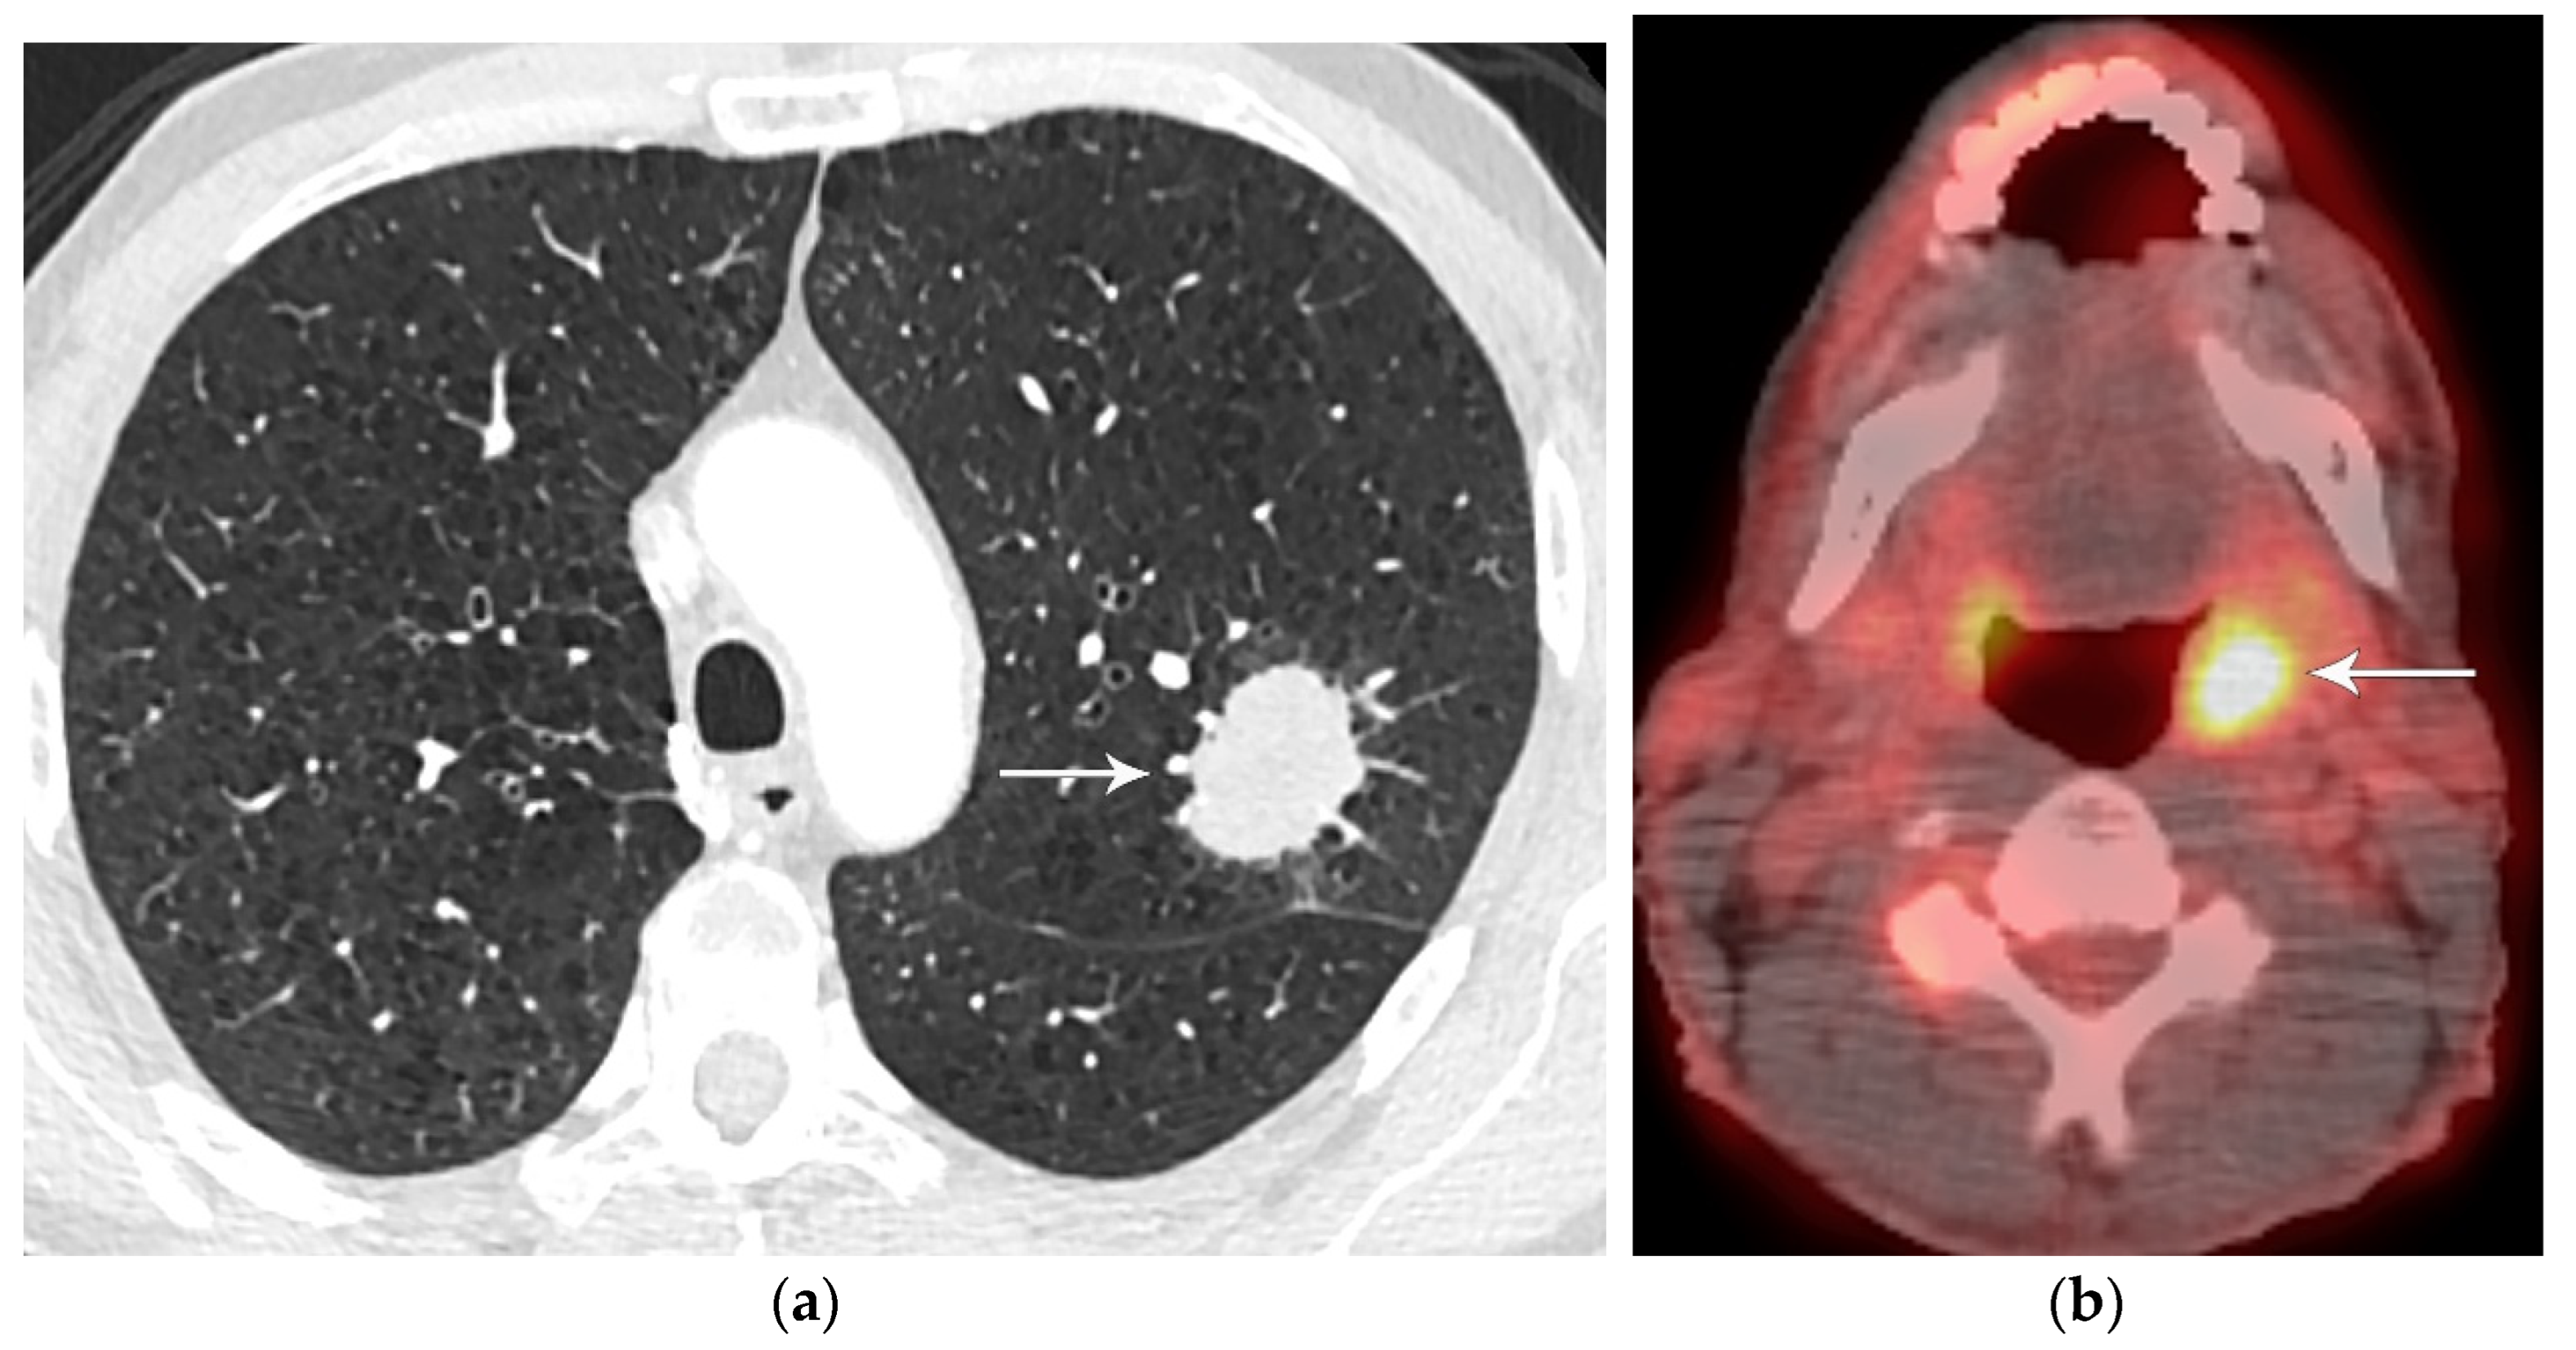

2. T Classification